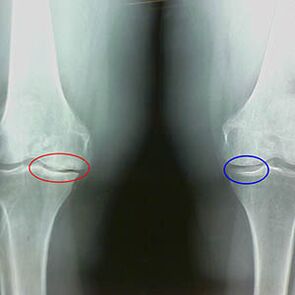

Determinatioun vum Grad vun Arthrosis geschitt duerch x -rayEntloossung Participatioun am pathologesche Prozess vu Knochenstrukturen. Hir Ännerung weist datt de Muskelystem an enger Ungléisung fir 5-10 Joer war. Als Regel, Leit Fir e puer Joer déi se erreechen. PéngAn.

Fréi x -An-Party Feature vun der zweeter Stuf vum Knie Arthrosis:

- Deen beschiedegt Kanten vun der Inter-fuberks op der Tibia, wou de Kräiz -shamed Ligament Ligament befestegt gëtt;

- Verengung vum Joint Spalt op der medialer Säit;

- De Promit markéiert d'KnŠrft an d'Rotschléi op der mëller Säiten, manner vill oft am Labetral - ofhängeg op der Entwécklung vum Valmgus an variéieren.

Fir déi zweet Etapp zu Larsen D'Verengung vum Joint Spalt vu méi wéi 50% ass charakteristesch, awer dëst kann nëmmen an Dynamik oder Verglach mat engem onwahrscheinlechen Gelenk gepréift ginn.